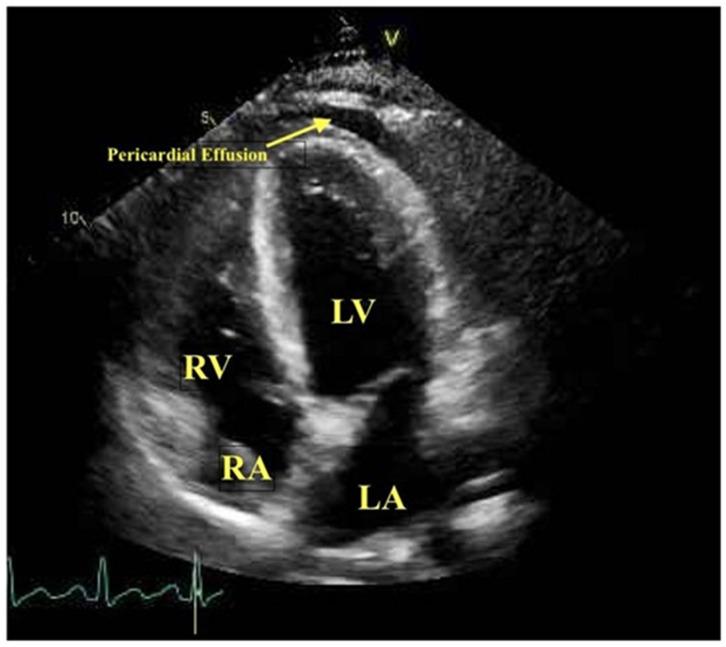

Viral myocarditis is inflammation of the myocardium secondary to viral infection. The clinical presentation of viral myocarditis is very heterogeneous and can range from nonspecific symptoms of malaise and fatigue in subclinical disease to a more florid presentation, such as acute cardiogenic shock and sudden cardiac death in severe cases. The accurate and prompt diagnosis of viral myocarditis is very challenging. Endomyocardial biopsy is considered to be the gold standard test to confirm viral myocarditis; however, it is an invasive procedure, and the sensitivity is low when myocardial involvement is focal. Cardiac imaging hence plays an essential role in the noninvasive evaluation of viral myocarditis. The current coronavirus disease 2019 (COVID-19) pandemic has generated considerable interest in the use of imaging in the early detection of severe acute respiratory syndrome coronavirus 2 (SARS-CoV-2)-related myocarditis. This article reviews the role of various cardiac imaging modalities used in the diagnosis and assessment of viral myocarditis, including COVID-19-related myocarditis.